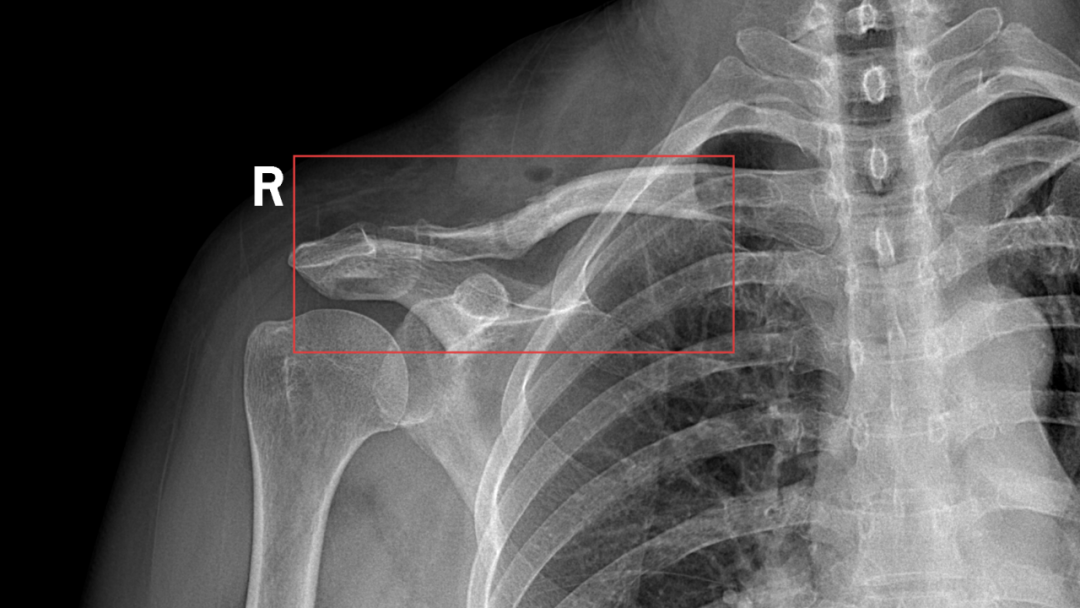

5月14日,玉溪市中山医院骨科为肩锁关节脱位术后患者武女士完成了内固定装置取出手术。一年前武女士因车祸导致右肩锁关节脱位 (III度),在玉溪市中山医院接受了“右肩锁关节脱位切开复位内固定术”,术后武女士积极配合医护团队治疗并顺利出院。此次术后一年复查,显示她的骨性愈合良好。骨科团队为武女士实施了精细化手术,顺利取出内固定装置,并通过精准操作确保患部功能完整恢复。术后,武女士恢复状况良好,于5月22日出院。为感谢周树文主任、杨鹏医师等医护团队,武女士赠送锦旗“妙手扶桑梓,高医攀新峰”,表达深切感激。

手术前